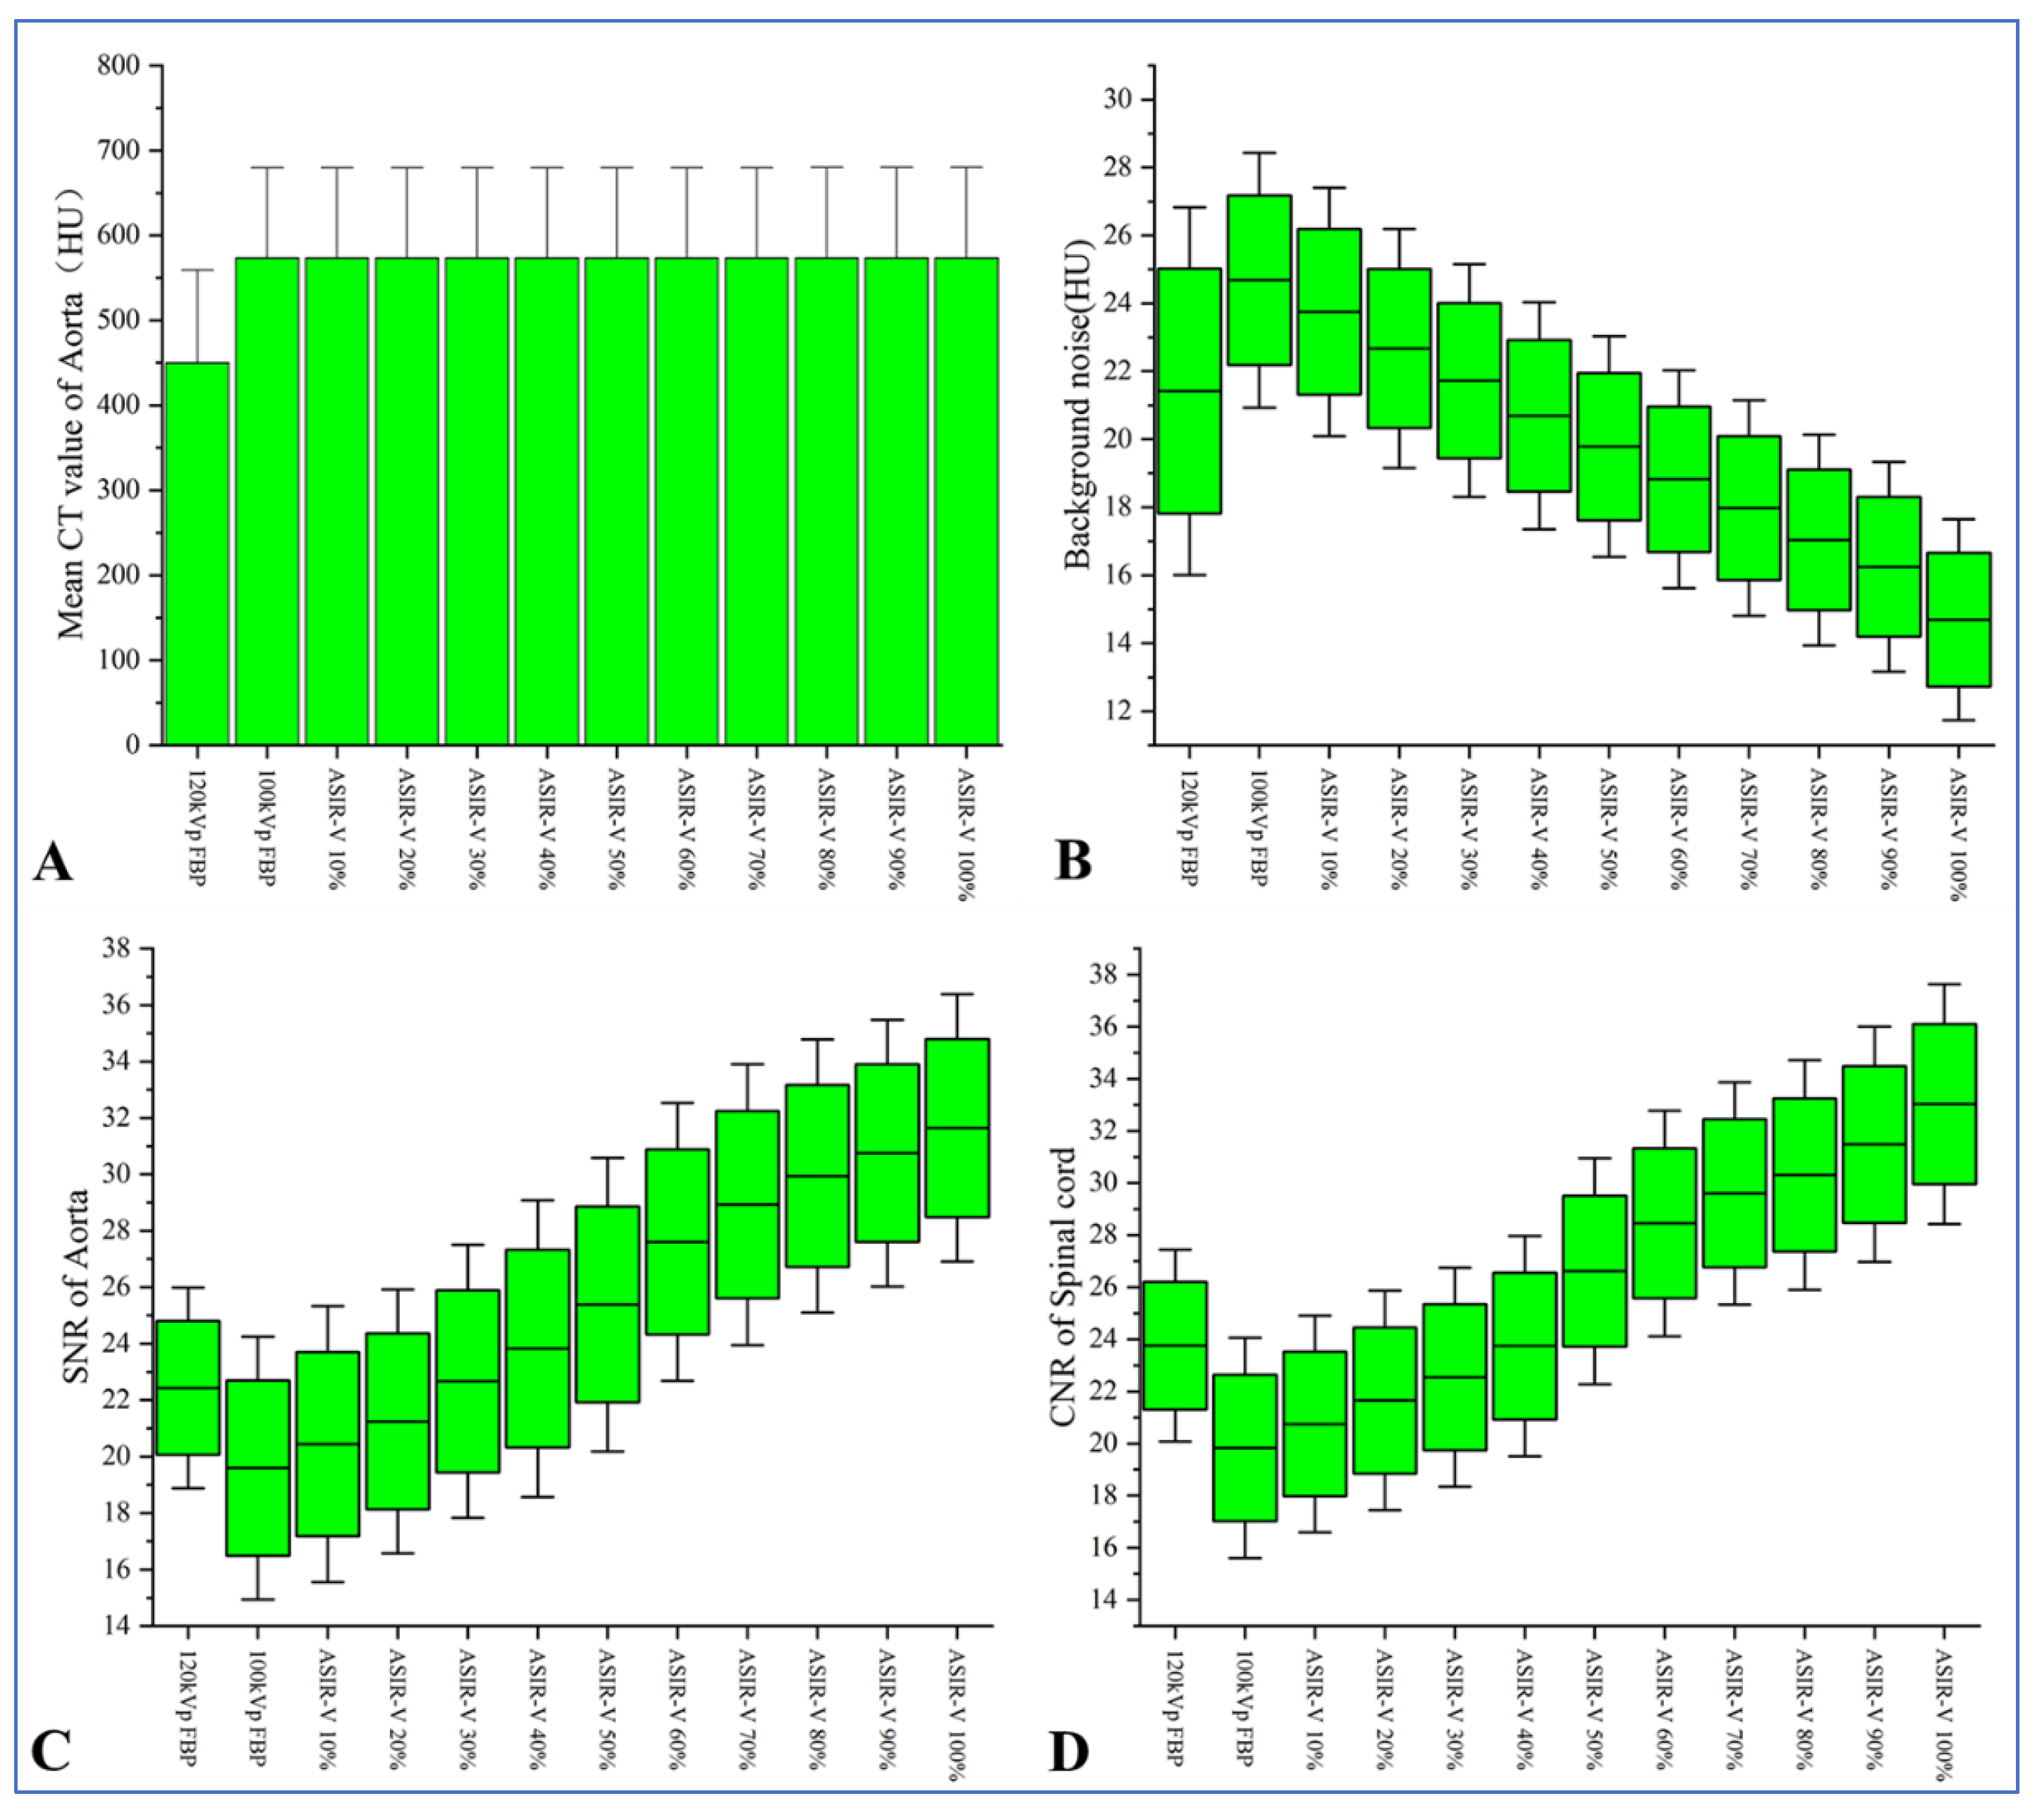

3.2. Objective Evaluation of Images

| Groups | Image Reconstruction Methods | CTAorta (HU) | Background Noise (HU) | SNRAorta | CNRSpinal cord |

|---|---|---|---|---|---|

| Group B | 120 kV FBP | 446.36 ± 71.41 | 21.42 ± 3.61 | 22.43 ± 2.37 | 23.76 ± 2.45 |

| Group A | 100 kV FBP | 573.86 ± 77.01 | 24.68 ± 2.50 | 19.59 ± 3.10 | 19.83 ± 2.81 |

| 100 kV ASIR-V 10% | 573.82 ± 77.02 | 23.75 ± 2.43 | 20.44 ± 3.26 | 20.74 ± 2.77 | |

| 100 kV ASIR-V 20% | 573.83 ± 77.03 | 22.67 ± 2.34 | 21.24 ± 3.12 | 21.65 ± 2.81 | |

| 100 kV ASIR-V 30% | 573.83 ± 77.04 | 21.72 ± 2.28 | 22.66 ± 3.23 | 22.54 ± 2.80 | |

| 100 kV ASIR-V 40% | 573.84 ± 77.05 | 20.69 ± 2.23 | 23.83 ± 3.50 | 23.75 ± 2.82 | |

| 100 kV ASIR-V 50% | 573.84 ± 77.06 | 19.78 ± 2.17 | 25.39 ± 3.47 | 26.61 ± 2.89 | |

| 100 kV ASIR-V 60% | 573.82 ± 77.10 | 18.82 ± 2.14 | 27.60 ± 3.28 | 28.45 ± 2.88 | |

| 100 kV ASIR-V 70% | 573.82 ± 77.11 | 17.97 ± 2.11 | 28.93 ± 3.32 | 29.60 ± 2.85 | |

| 100 kV ASIR-V 80% | 573.83 ± 77.15 | 17.04 ± 2.07 | 29.94 ± 3.23 | 30.31 ± 2.94 | |

| 100 kV ASIR-V 90% | 573.87 ± 77.16 | 16.25 ± 2.06 | 30.75 ± 3.15 | 31.48 ± 3.01 | |

| 100 kV ASIR-V 100% | 573.95 ± 77.18 | 14.69 ± 1.97 | 31.65 ± 3.16 | 33.03 ± 3.07 | |

| H Value | 84.786 | 386.666 | 391.562 | 439.635 | |

| p value | <0.001 | <0.001 | <0.001 | <0.001 |